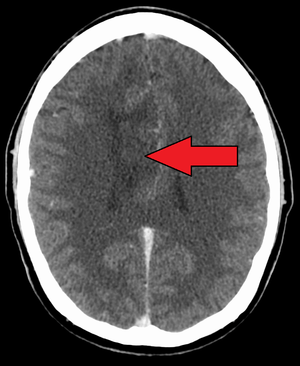

| A oligoastrocytoma on CT | |

An X-ray computed tomography (CT) or magnetic resonance imaging (MRI) scan is necessary to characterize the anatomy of this tumor as to size, location, and its heter/homogeneity. However, final diagnosis of this tumor, like most tumors, relies on histopathologic examination (biopsy examination).